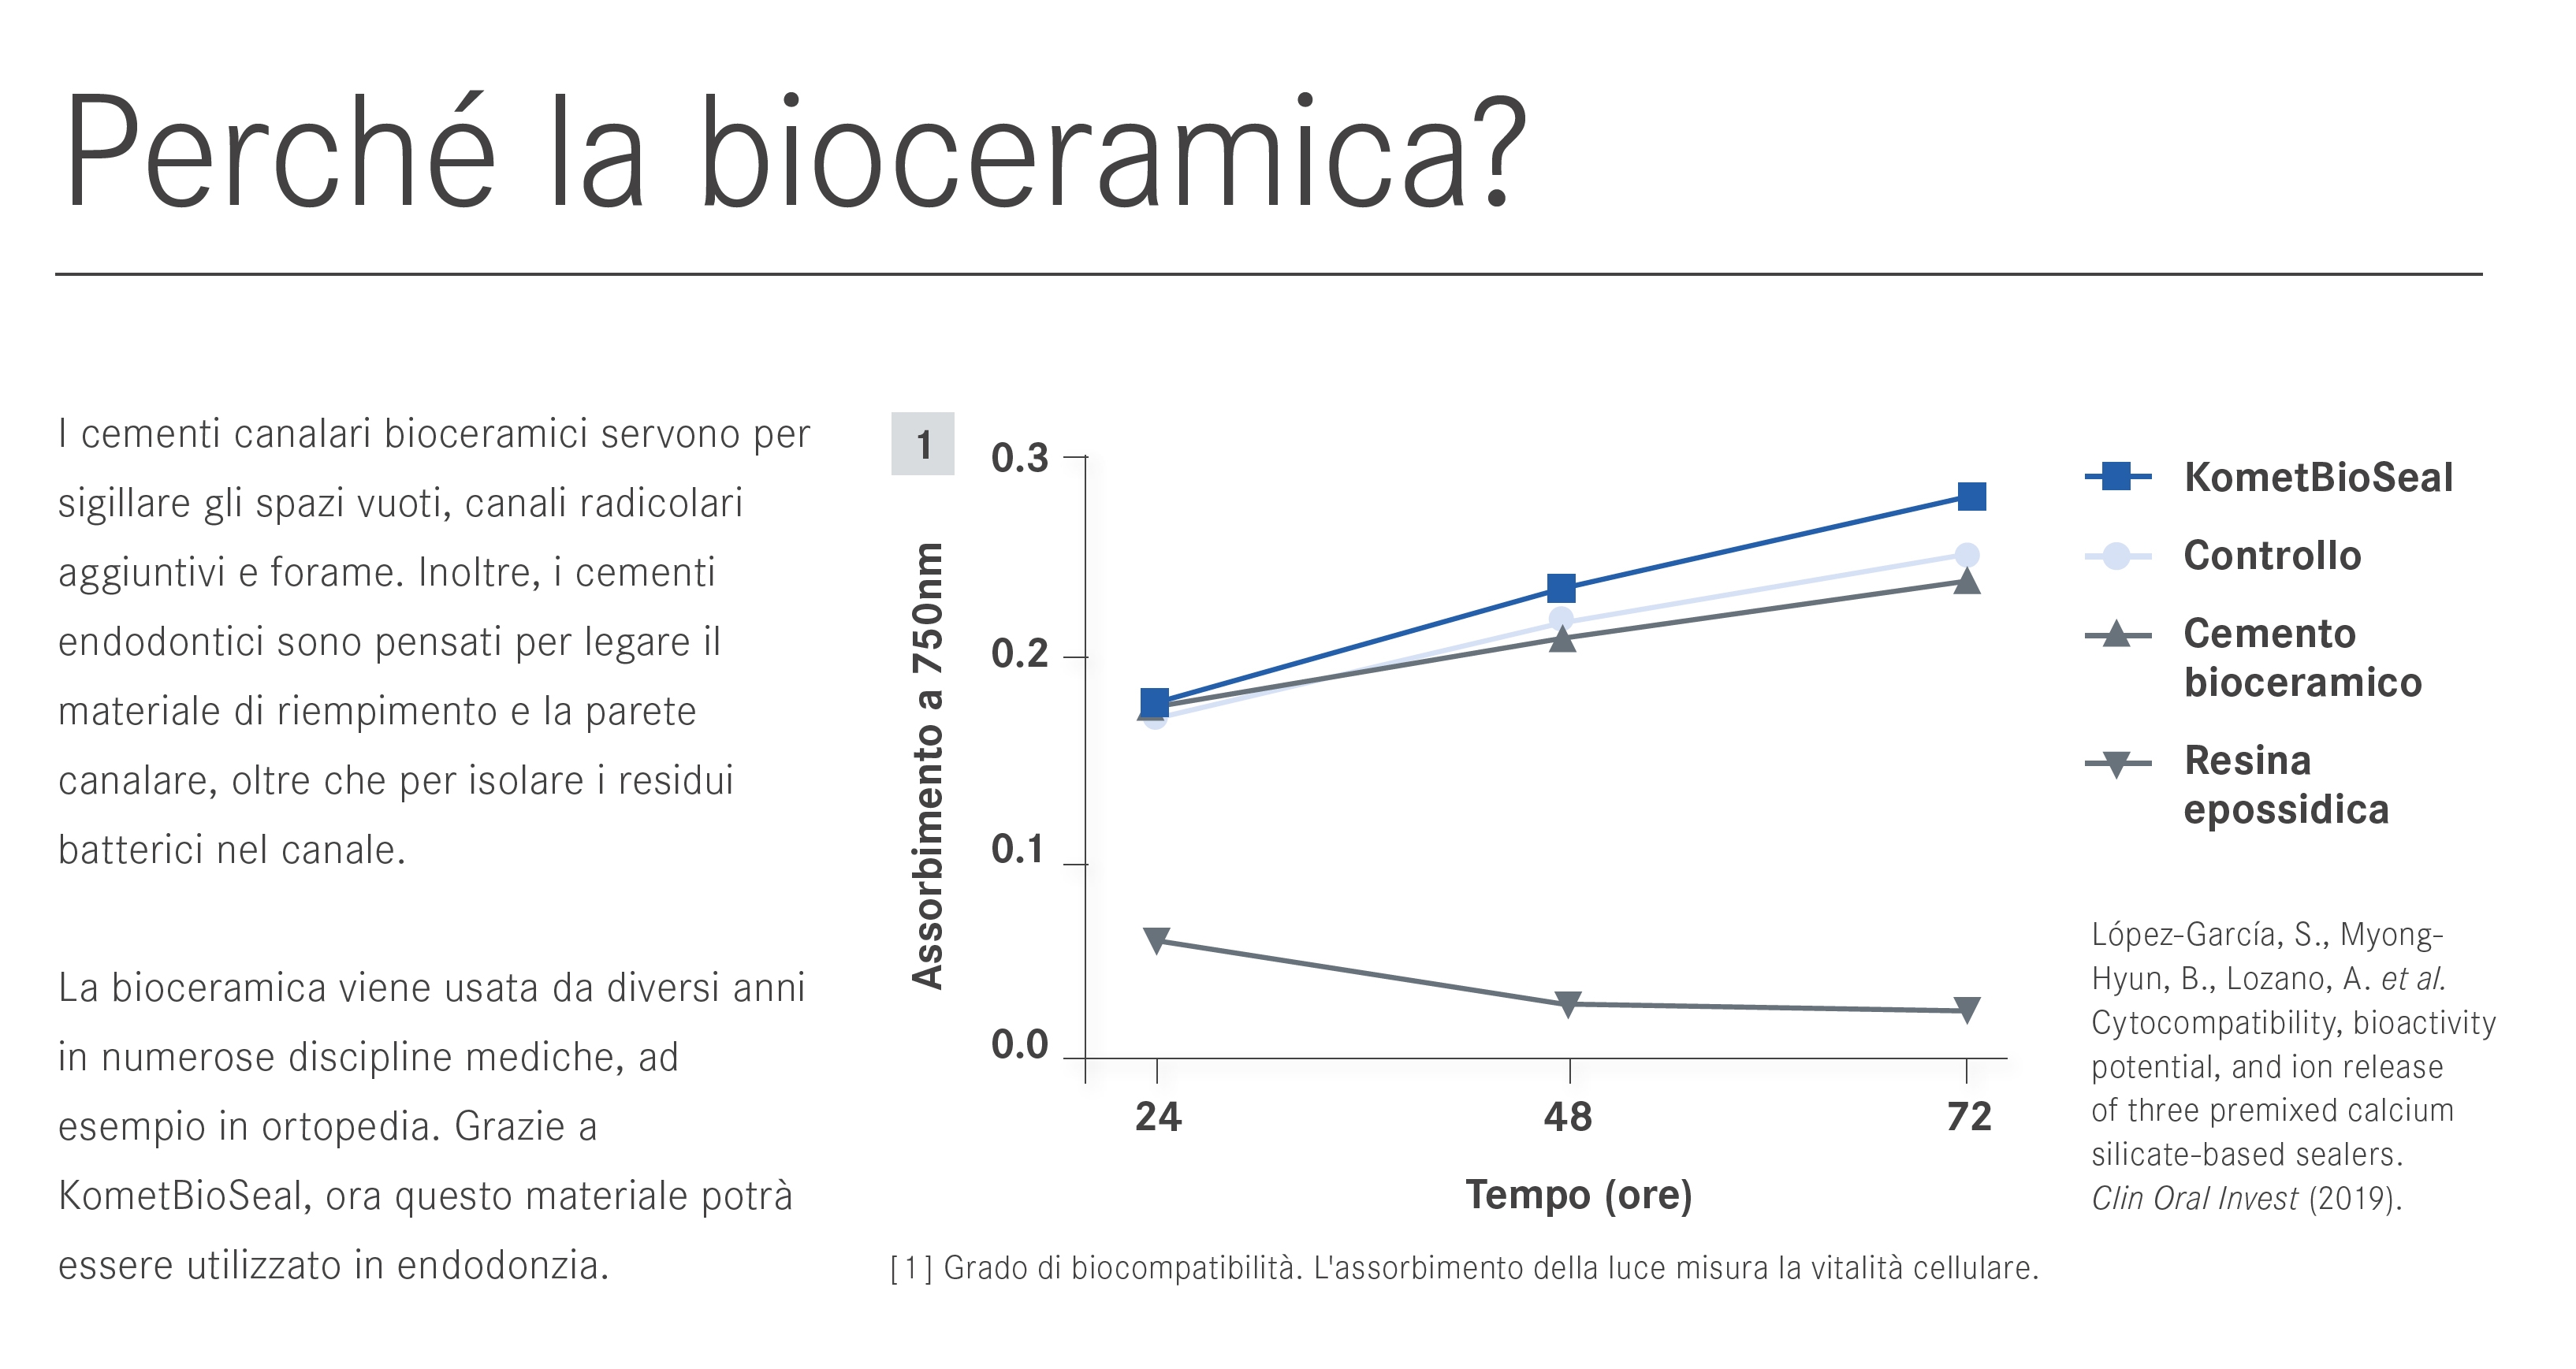

La chiusura è effettuata con cono singolo e bioceramico Komet BioSeal.

Trattamento endodontico di un incisivo laterale superiore con due radici - parte 12La chiusura è effettuata con cono singolo e bioceramico Komet BioSeal.